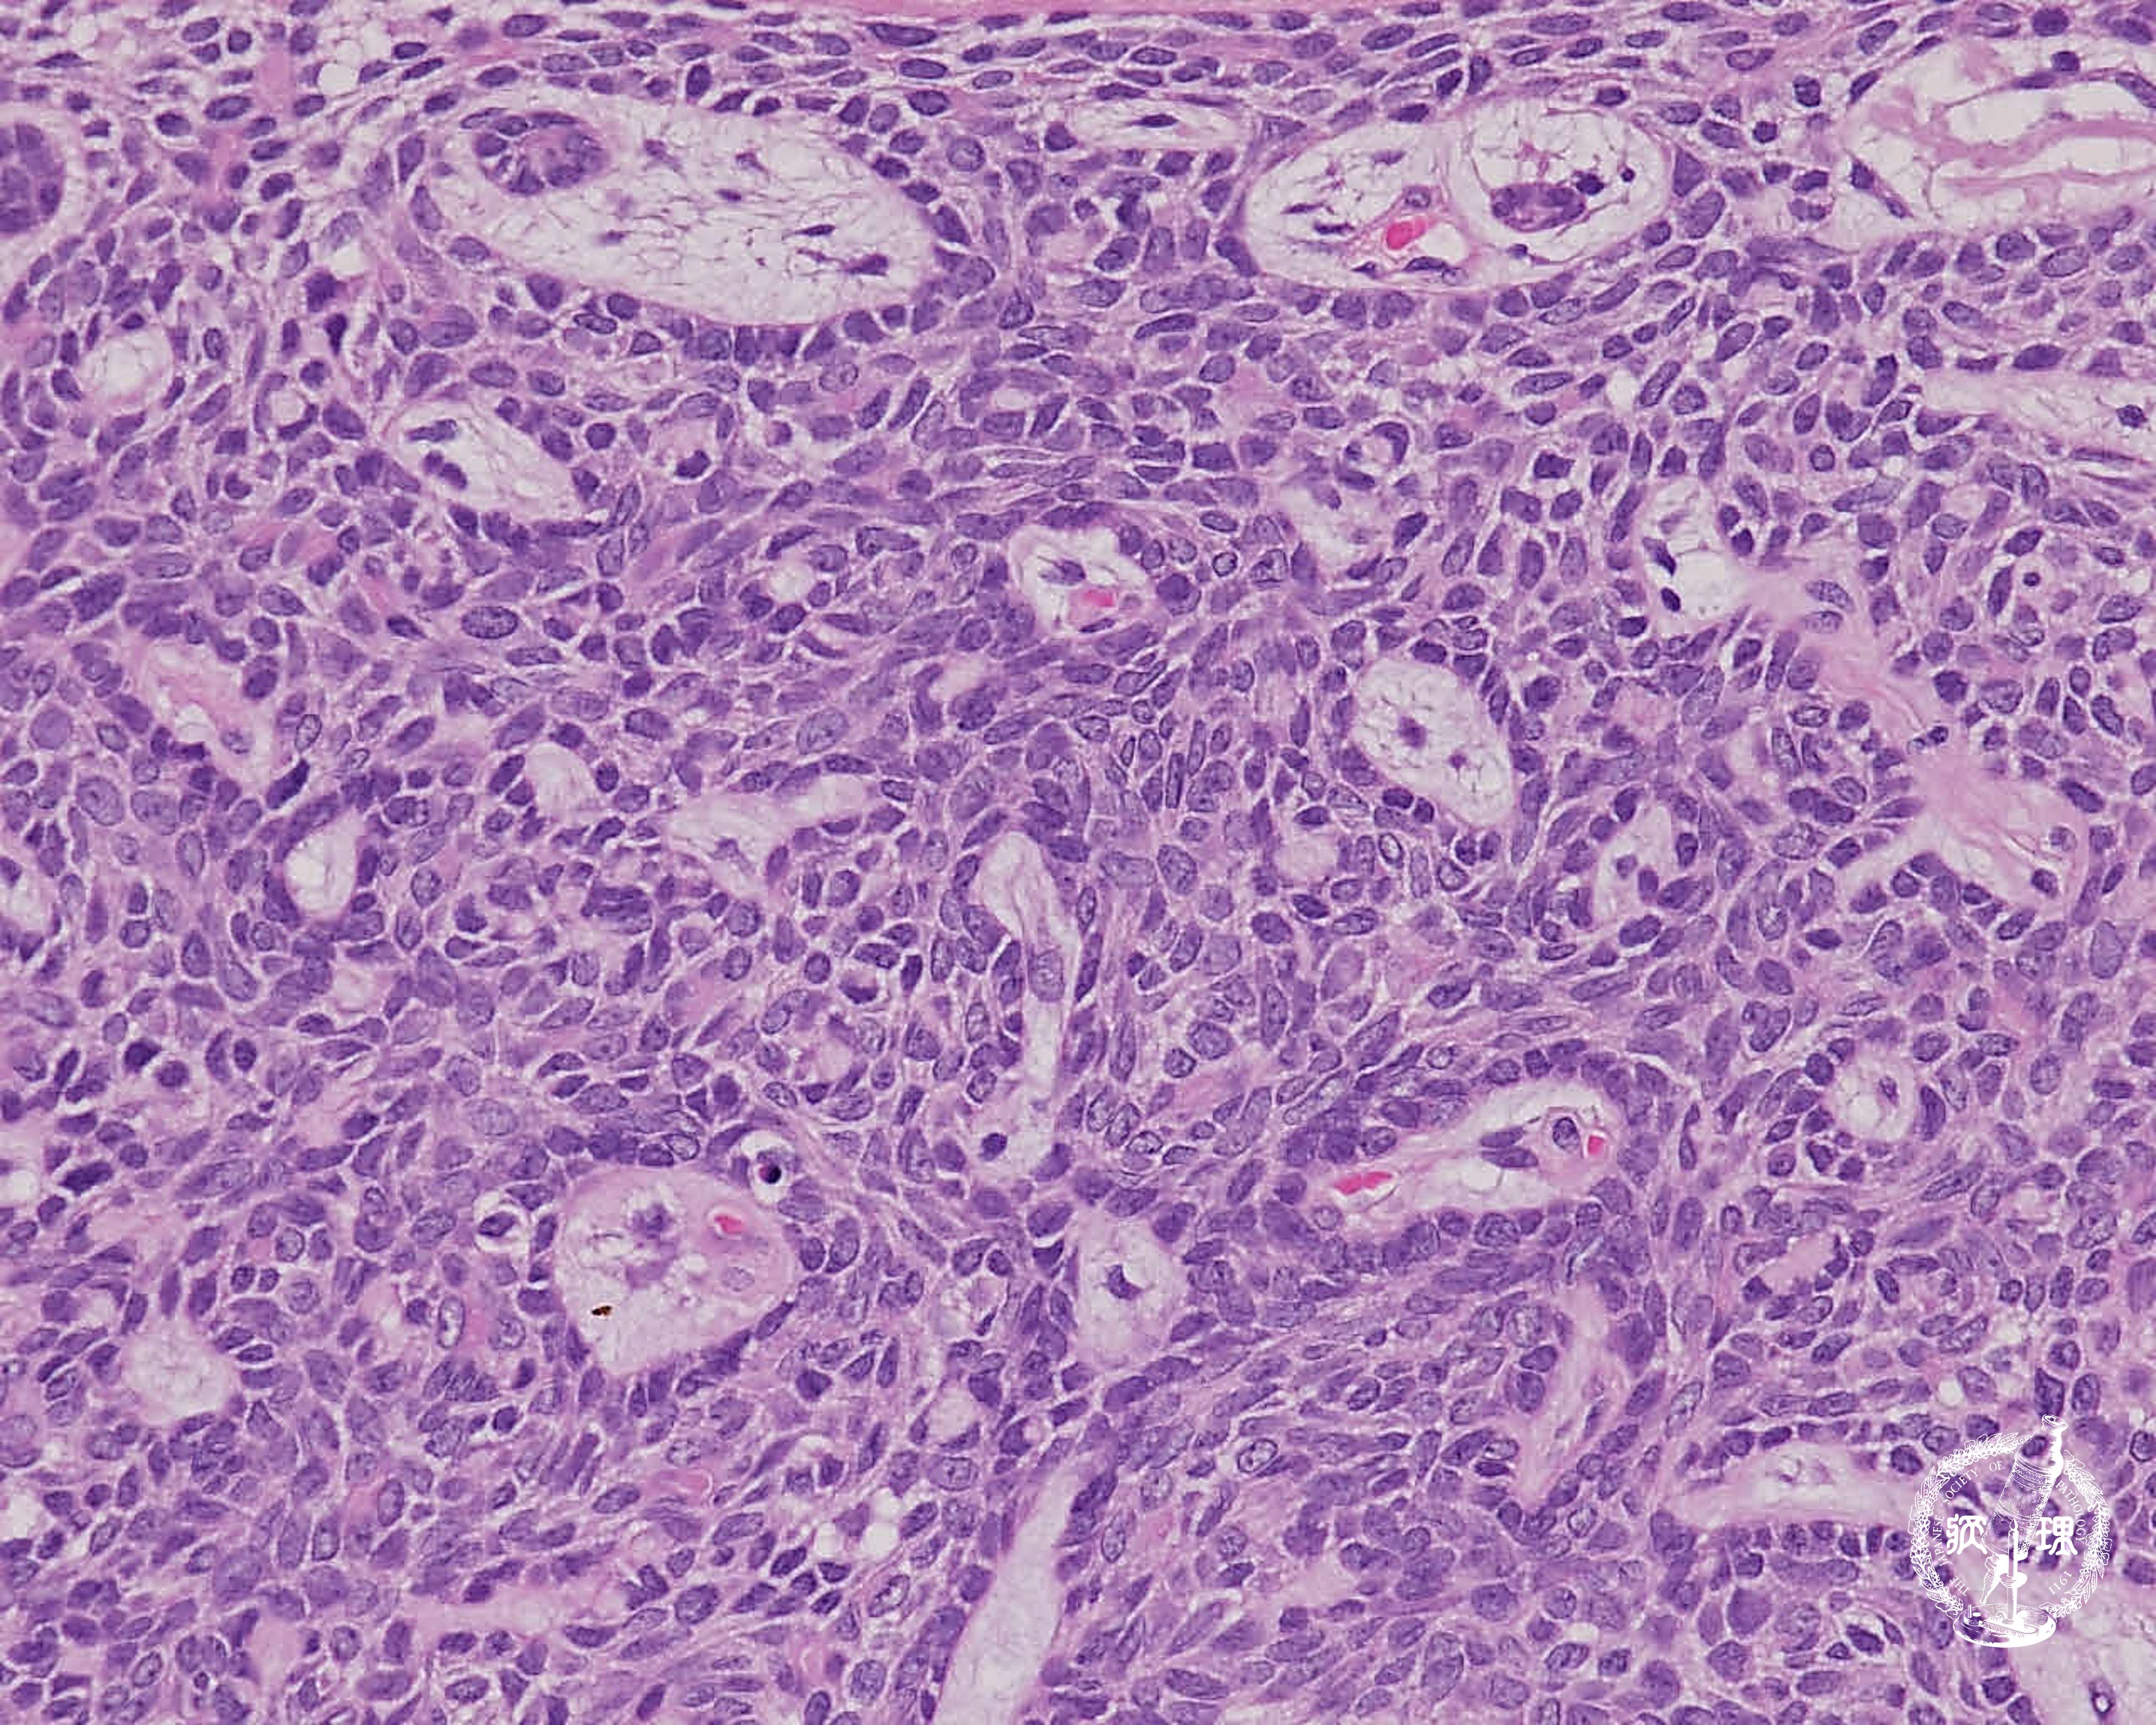

• 唾液腺腫瘍 (基底細胞腺腫)